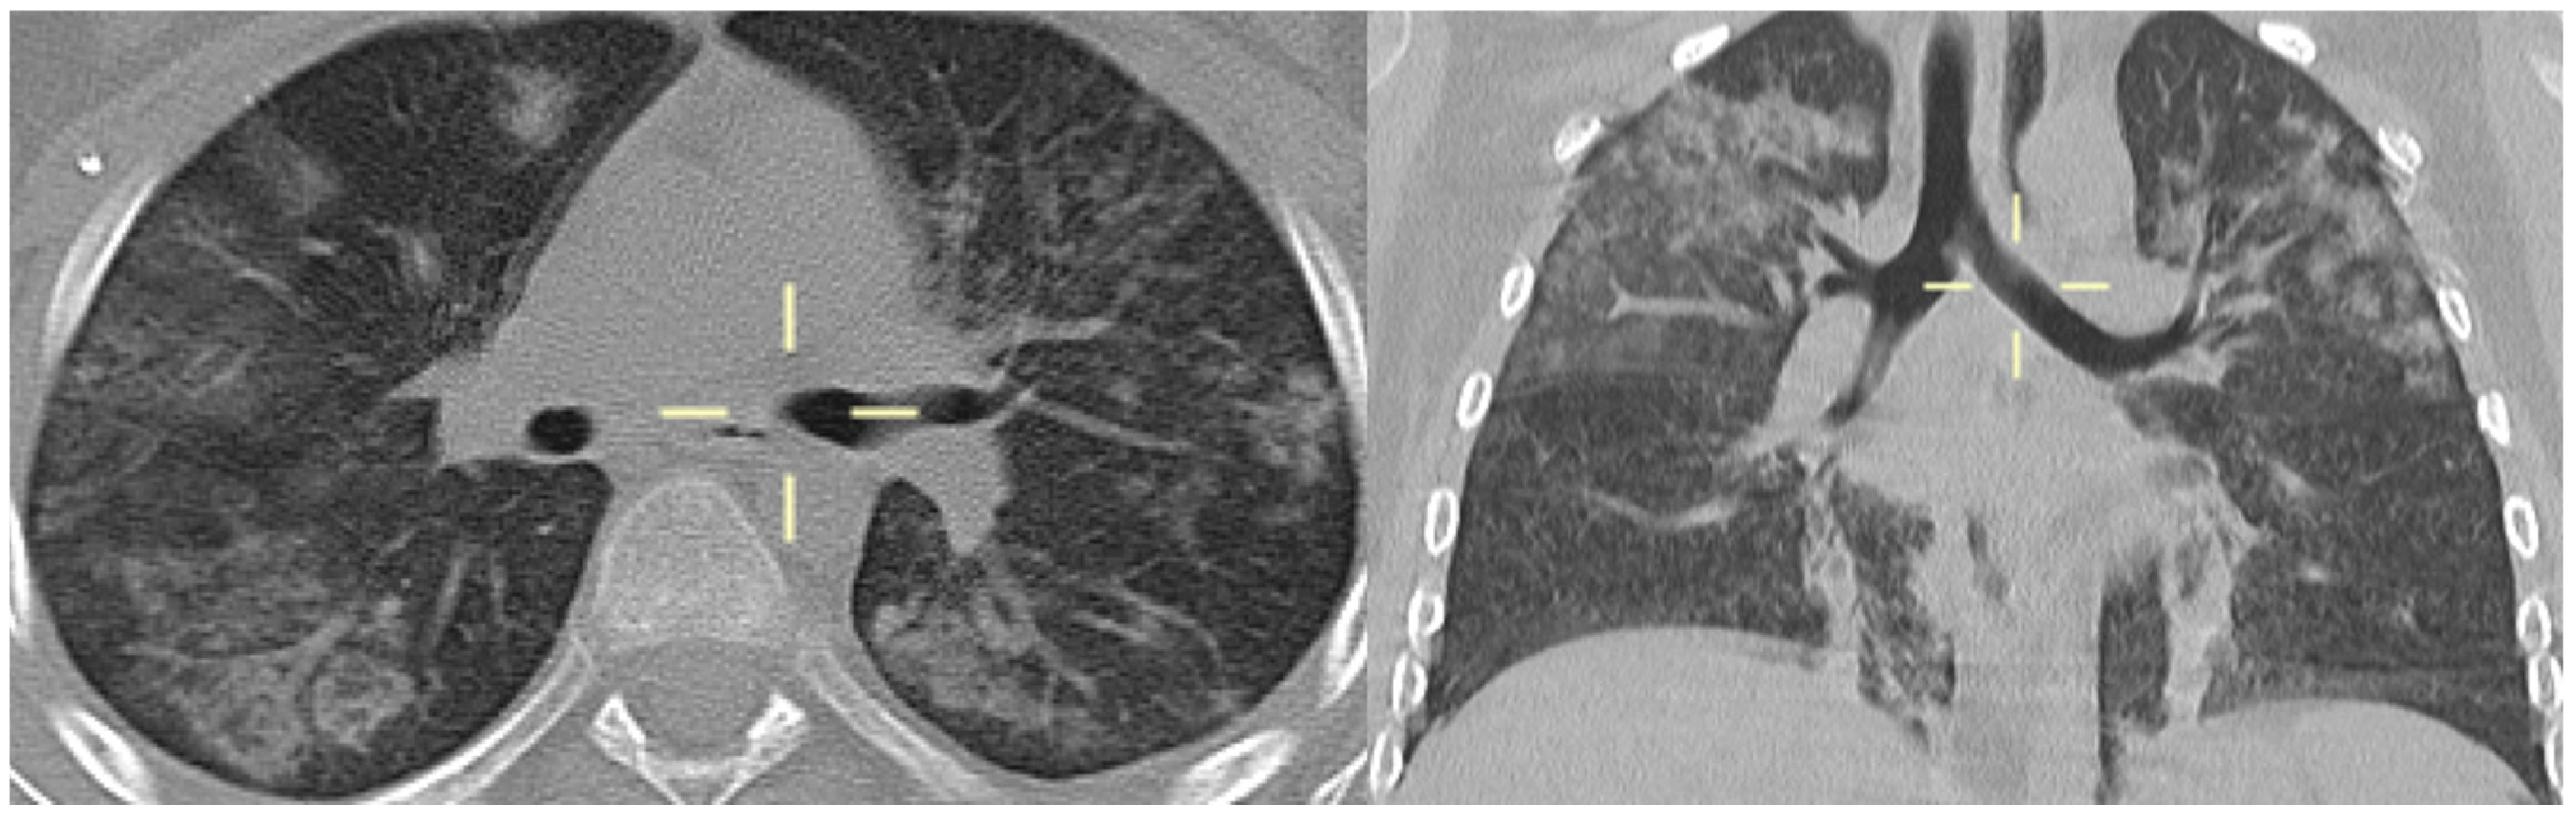

3.5. Radiological Features of PJP in the Study Population